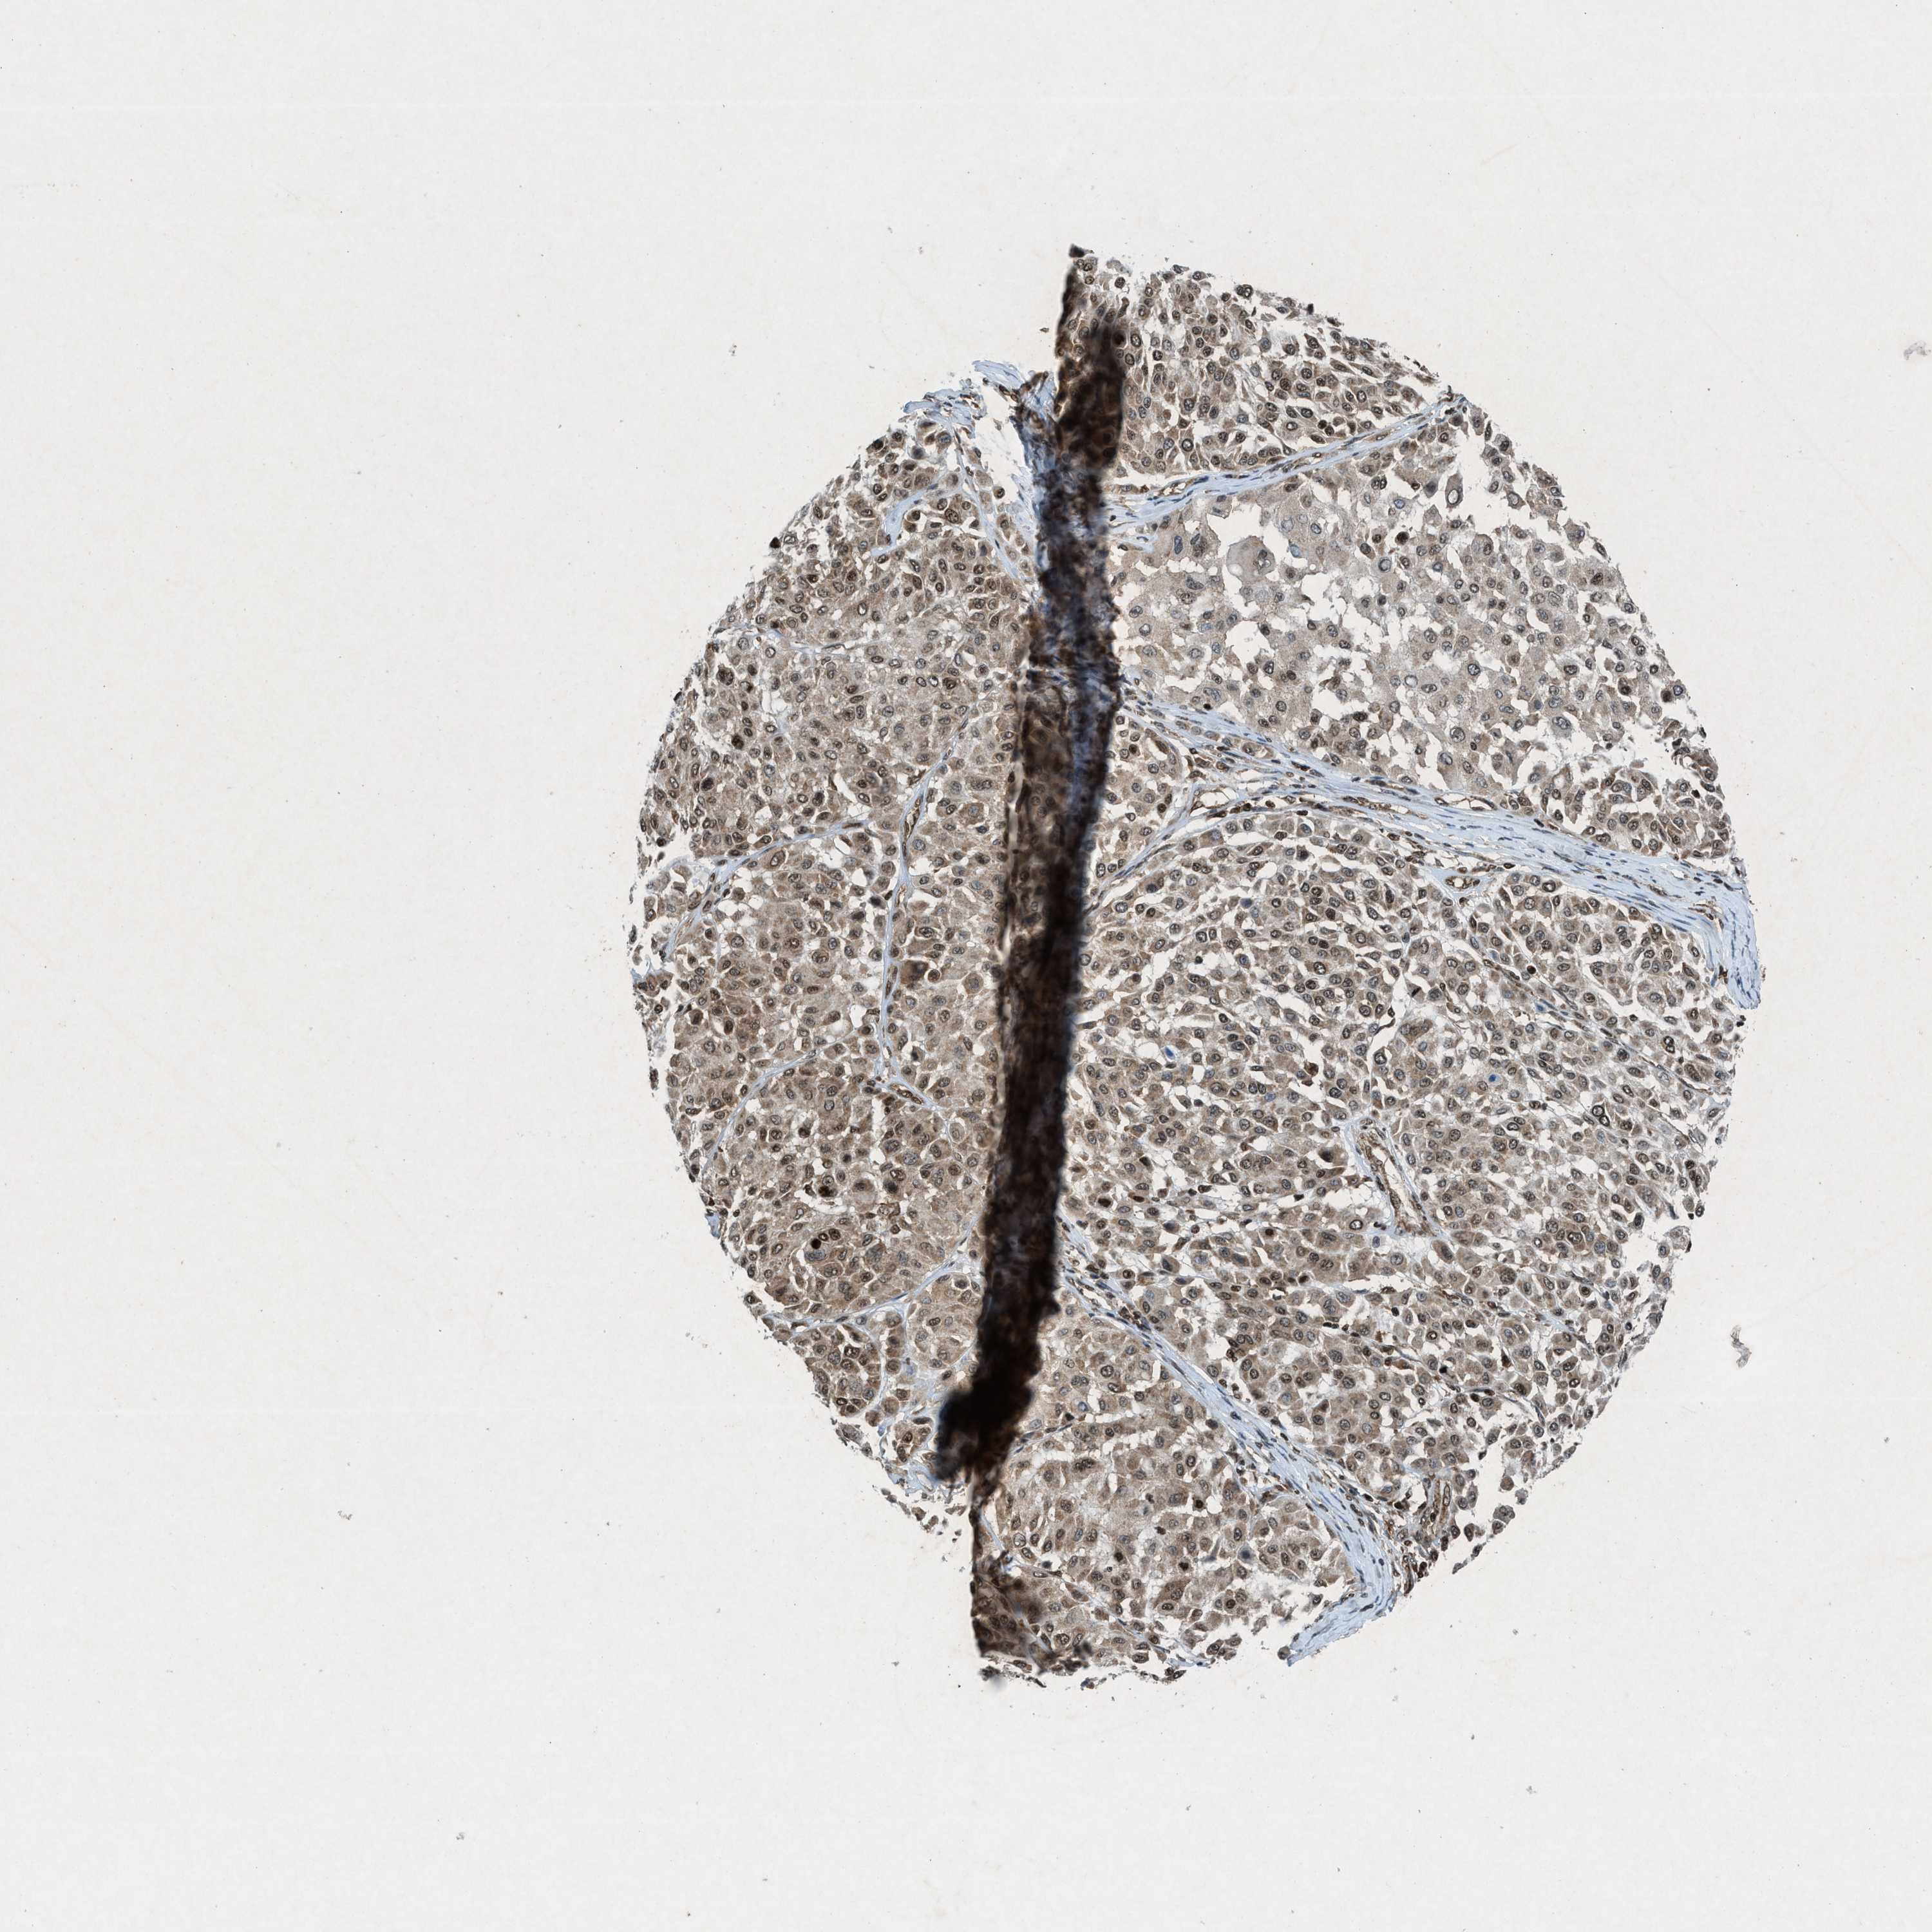

MELANOMA - Protein expressioni

A mouse-over function shows sample information and annotation data. Click on an image to view it in a full screen mode. Samples can be filtered based on level of antibody staining by selecting one or several of the following categories: high, medium, low and not detected. The assay and annotation is described here.

Note that samples used for immunohistochemistry by the Human Protein Atlas do not correspond to samples in the TCGA dataset.

Antibody stainingi

Antibody staining in the annotated cell types in the current human tissue is reported as not detected, low, medium, or high, based on conventional immunohistochemistry profiling in selected tissues. This score is based on the combination of the staining intensity and fraction of stained cells.

Each image is clickable and will lead to virtual microscopy that enables deeper exploration of all samples and also displays staining intensity scores, fraction scores and subcellular localization as well as patient and tissue information for each sample.

Antibody HPA061593

Antibody CAB016327

Staining

High

Medium

Low

Not detected

Intensity

Strong

Moderate

Weak

Negative

Quantity

>75%

75%-25%

<25%

None

Location

Nuclear

Cytoplasmic/membranous

Cytoplasmic/membranous,nuclear

Malignant melanoma, NOS

Malignant melanoma, Metastatic site